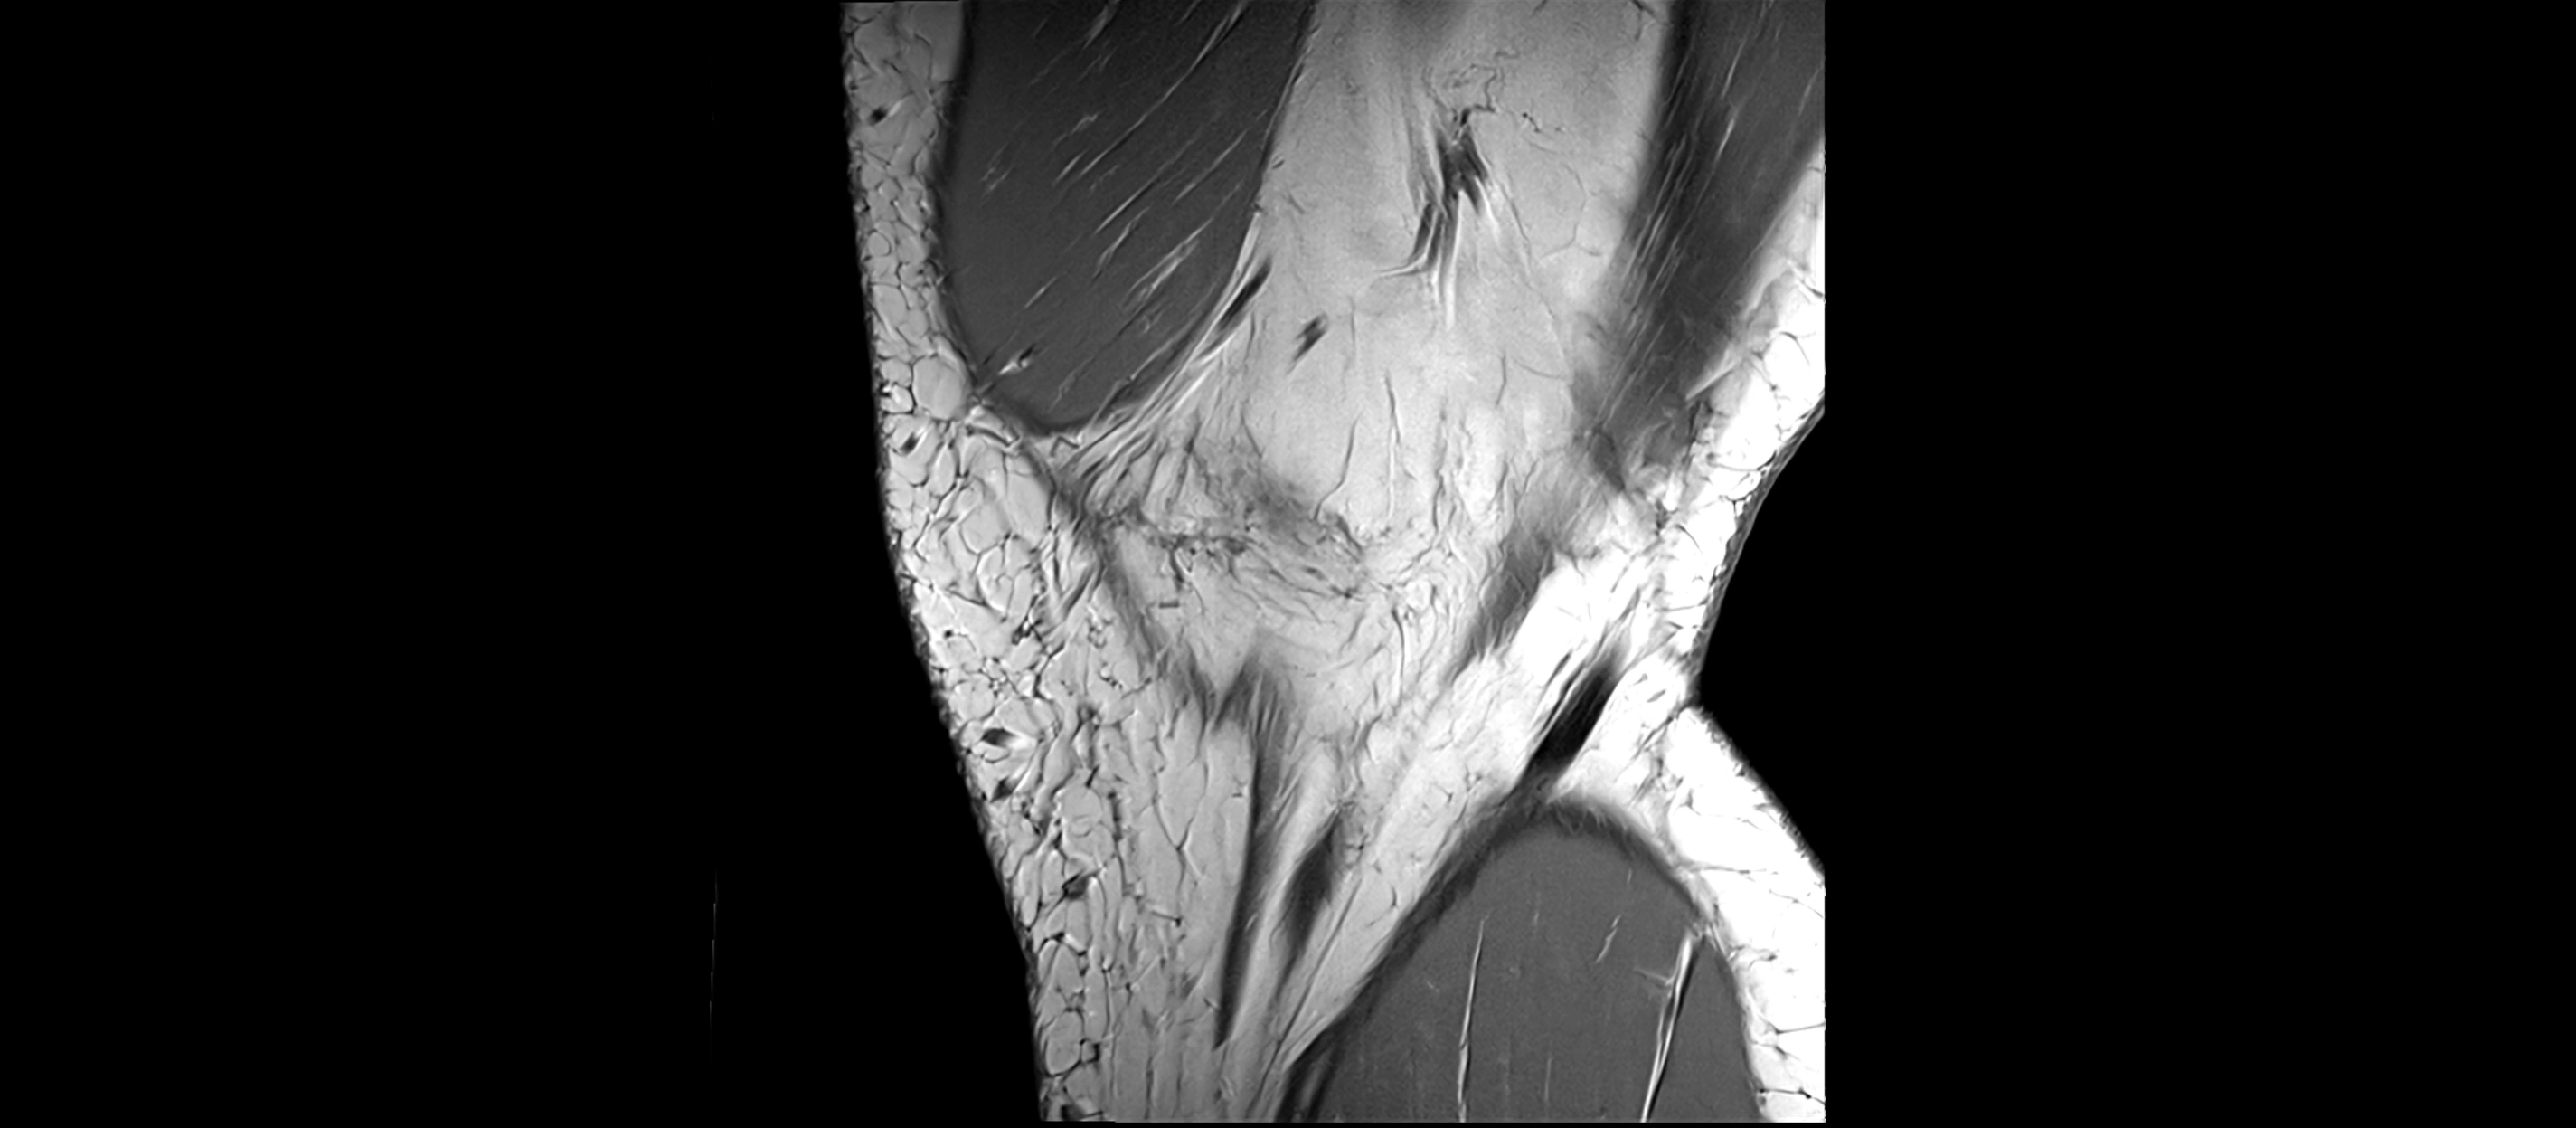

MRI images

image

CT image